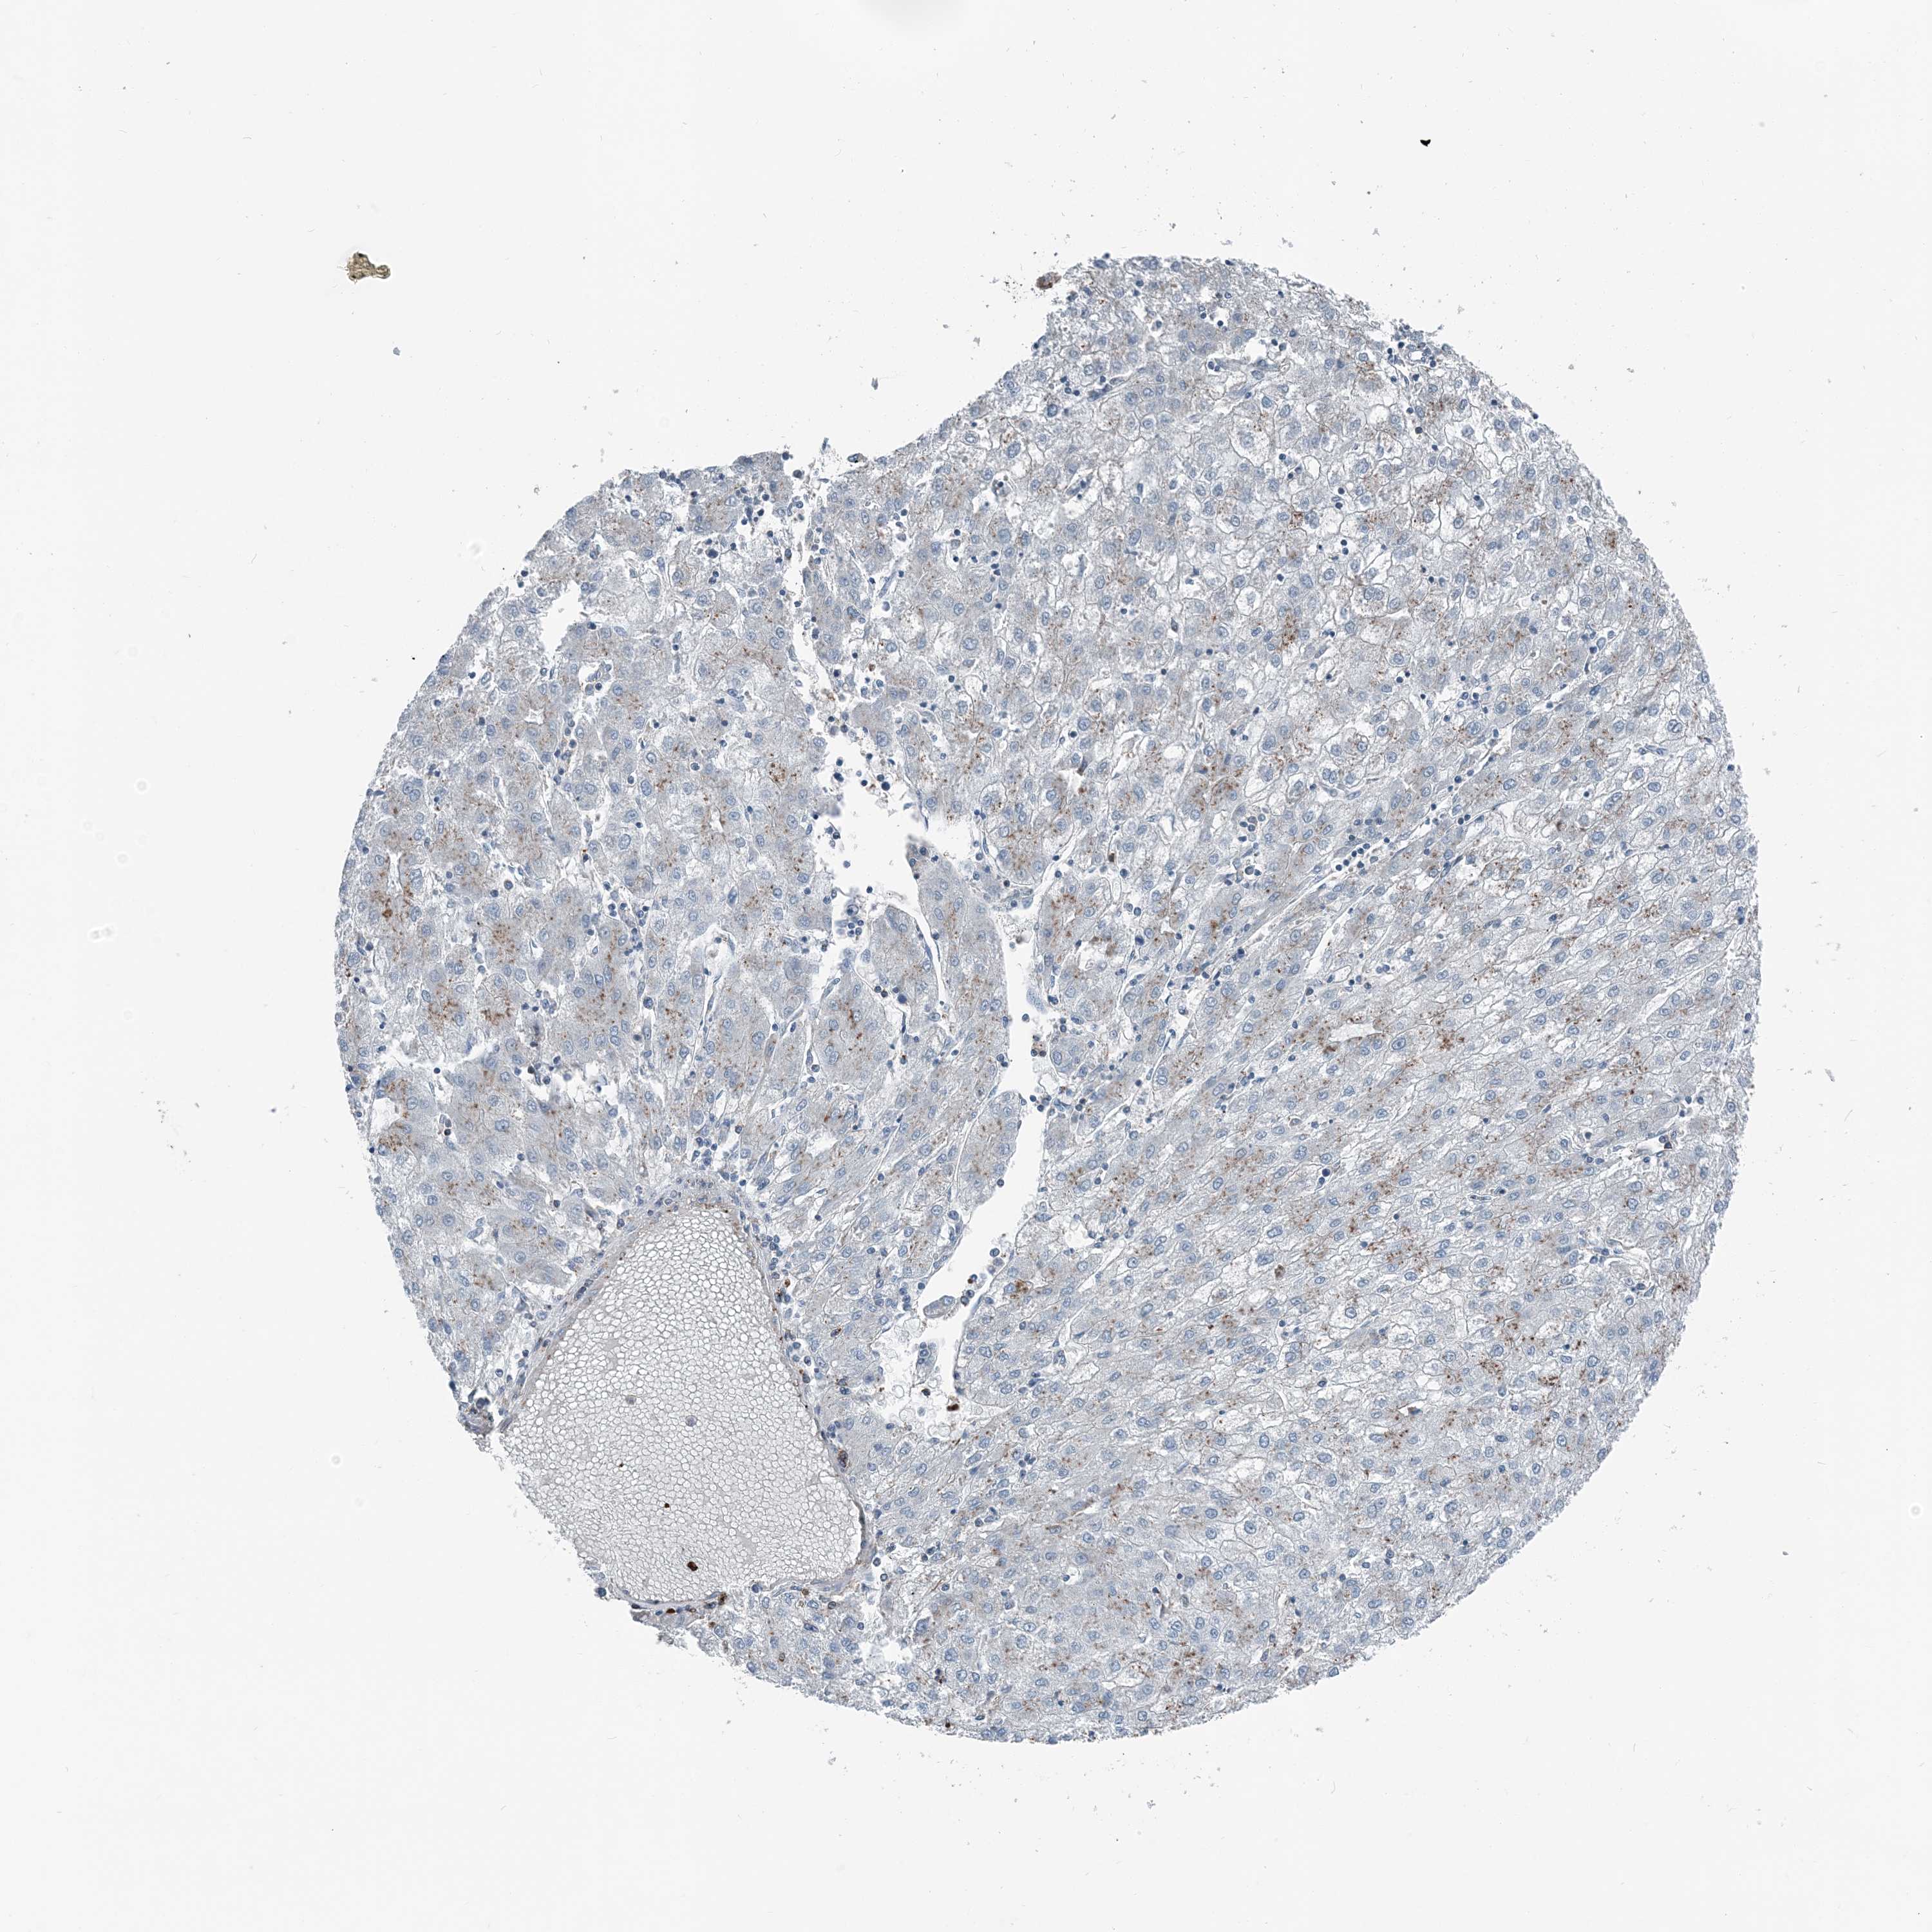

LIVER CANCER - Protein expressioni

A mouse-over function shows sample information and annotation data. Click on an image to view it in a full screen mode. Samples can be filtered based on level of antibody staining by selecting one or several of the following categories: high, medium, low and not detected. The assay and annotation is described here.

Note that samples used for immunohistochemistry by the Human Protein Atlas do not correspond to samples in the TCGA dataset.

Antibody stainingi

Antibody staining in the annotated cell types in the current human tissue is reported as not detected, low, medium, or high, based on conventional immunohistochemistry profiling in selected tissues. This score is based on the combination of the staining intensity and fraction of stained cells.

Each image is clickable and will lead to virtual microscopy that enables deeper exploration of all samples and also displays staining intensity scores, fraction scores and subcellular localization as well as patient and tissue information for each sample.

Cholangiocarcinoma

Carcinoma, Hepatocellular, NOS